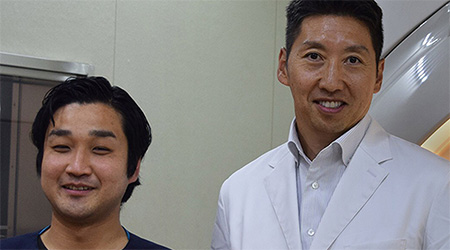

Dr. Mark Oswood, MD, PhD, Neuroradiologe, Hennepin Healthcare, Minneapolis, USA

Mit freundlicher Genehmigung von: Kurashiki Zentralkrankenhaus, Okayama. Japan

Dr. Takashi Koyama, MD, PhD, diagnostischer Radiologe und Leiter des Radiologiezentrums und der diagnostischen Radiologie, Kurashiki Zentralkrankenhaus, Japan

Sachi Fukushima, MTRA, Kurashiki Zentralkrankenhaus, Japan

Compressed SENSE kann die meisten MR-Scansequenzen ohne Kompromisse bei der Bildqualität beschleunigen. Dadurch konnte die KOYASU Neurochirurgische Klinik (KNC) ihre Nutzungsdauer für MR-Untersuchungen verkürzen und den Durchsatz ihrer MR-Scanner um durchschnittlich drei zusätzliche Patienten pro Tag erhöhen.

Schnelle Scans mit hoher Qualität am KCH

Das MR-Team am Kurashiki Zentralkrankenhaus nutzt Compressed SENSE in den meisten seiner Untersuchungsprotokolle für Gehirn, Wirbelsäule, Abdomen und Herz auf seinem Ingenia 1.5T. Patienten und Mitarbeiter begrüßen gleichermaßen die schnellen und hochwertigen MR-Scans.